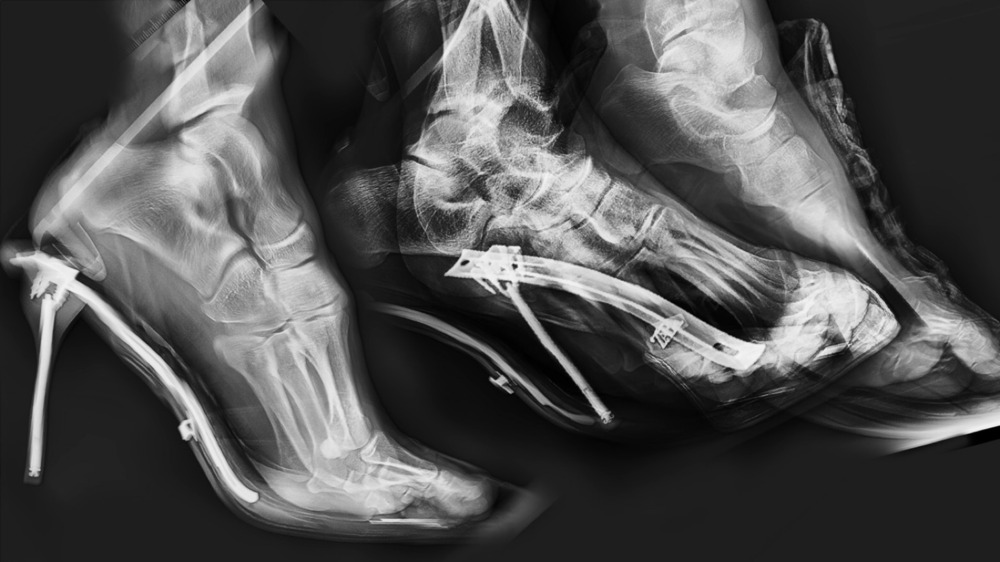

이후 작가는 신체의 이미지를 매개하는 기계적 장치들—카메라, X-ray, 의료기기—에 주목했다. 《Glove box》에서는 이 장비들을 단순한 기록 도구가 아닌 ‘통제의 구조’로 전환시켰다. 전시장 안에 놓인 영상과 오브제들은 해부와 응급처치, 관찰의 시점을 교차시키며, 몸이 더 이상 ‘나’의 일부로만 남지 못하는 감각을 구축한다. 특히 〈Ray〉는 인간의 욕망을 X-ray 영상과 겹쳐 보여주며, 내부와 외부, 생명과 무생명 사이의 경계를 해체한다.

네마프 영화제 출품작 〈Cardiopulmonary Resuscitation / 1S34008AP, F010122011964, .04. 0*8. 5mm〉와 〈Ray〉(2024)에서 작가는 생명과 사망의 경계에 놓인 몸, 마취된 신체의 감각, 그리고 그것을 시각화하는 장치의 냉정함을 관객에게 드러낸다.